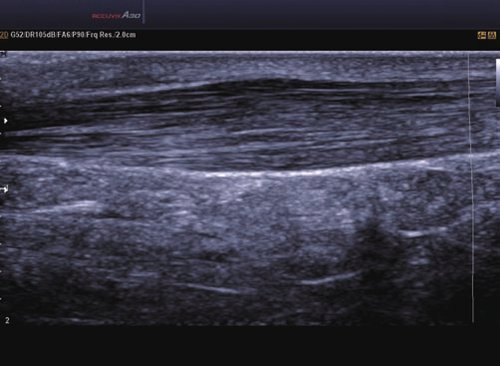

1 L4-7 Linear 4-7 MSK, Gefäße, Tiefe Venen

2 L5-13IS Linear 6-12 MSK, Weichteile, Gefäße, Brust

3 L5-13/50mm Linear 5-13 MSK, Weichteile, Gefäße

4 LS6-15 Linear 6-15 MSK, Weichteile, Gefäße

5 L7-16IS Linear 7-16 MSK, Weichteile, Gefäße, weibliche Brust, Pädiatrie, Oberfläche

• ElastoScan™ ermöglicht eine genauere Visualisierung von Tumoren und erfasst und dokumentiert Gewebesteifheiten.

• Das Tissue Specific Imaging (TSI) optimiert die Qualität des Scans anhand der Beschaffenheit des Gewebes. Es kann aus 4 unterschiedlichen Bildmodi gewählt werden: Allgemein, Muskel, Fließend, Fett.